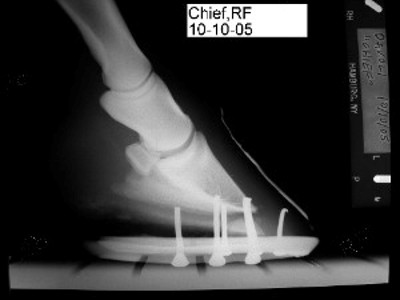

i am attaching xrays and photos of his left front. xrays are from 10/05 and 6/06. photos are from 6/06.

hi, thanks Holly!! i have just hopefully gotten these xrays sized right....

lf

lt

Certainly many of the problems you describe are related to the conformation of the front feet and if I understand your post properly I disagree with your veterinarians assessment of the degree of rotation of the coffin bone in each of the radiographs above. He is apparently drawing a line from the proximal wall rather than looking at the distal wall or the relationship with the ground. I would calculate the difference of the measured angle of the bottom of the coffin bone with a more normal 6 degree tilt and call that the degree of rotation.

Here is the problem: is this rotation because of past founder or because of primary flexor contracture (ie club feet). The two will look similar at this point though the upright pasterns may tip the scales a bit to flexor contracture. If it is decided it is the former, much can be done to return these feet to normal. It it is the latter we are stuck with this.

I guess he believes this is due to flexor contracture which will not respond to lowering the heels. However I have seen dozens of horses derotated following founder episodes and we have many reports of it on these boards. I have to say his attitude does leave me nonplussed but if your problems are the result of flexor contracture, he will be mostly correct about this horse but his lack of attention to the flare in a tripping horse and the obvious lack of heel support, both evident in the radiographs, are areas that could be addressed in any case in my opinion. I will be interested to hear the second opinion and I want you to develop an open mind to both possibilities however. If you go doing remarkable heel lowering and their is no room for flexor stretching/relaxation you will have to nurse this foot back to its current conformation.

The feet do look better valerie, but if the horse is lame from the shoeing it suggests we may be doing something wrong. It is important to try and localize the lameness. The radiographs and the manner in which the heels were lowered suggest that soreness is coming from excessive thinning at the sole of the toe. It appears the farrier lowered the heels by cutting a wedge that extends from the heel to the toe. I spent years making horses sore by doing that. Instead a wedge taken from the heels to the quarters, then rotating the sole of the toe off the ground gives better results. On the other hand if the horse is landing flat on this it does suggest we have the room to improve this horses angles. See the article on derotation for pictures of this.